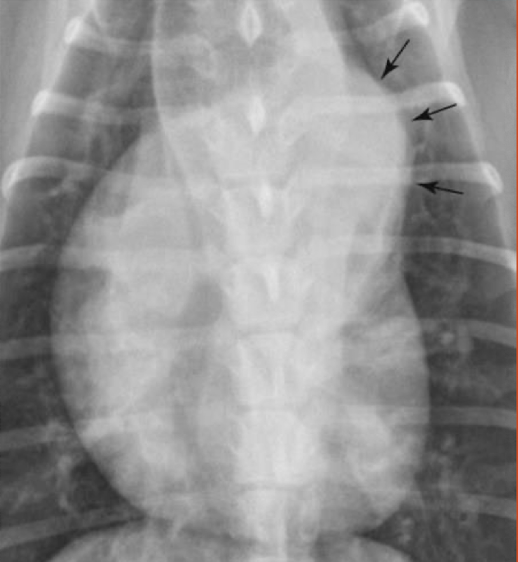

What are the arrows pointing to? Pattern?

Lobar signs

alveolar pattern